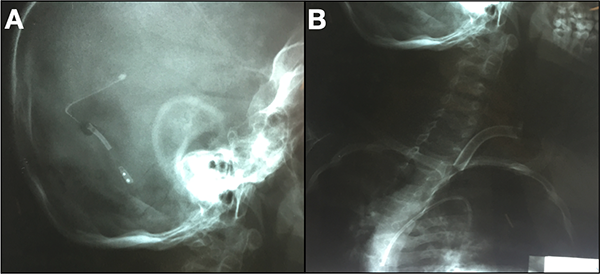

Complicaciones tardías: un paciente consultó dos años después del procedimiento con clínica de hipertensión endocraneana y se observó desprendimiento del catéter distal, ubicado en cavidades cardiacas derechas (Figura 7). Además, hubo 2 casos de infecciones secundarias a sepsis de foco sistémico y siete casos de disfunción proximal.

Figura 7: A) Radiografía cráneo perfil donde se observa el catéter ventricular y la válvula, pero no se observa el catéter distal. B) Radiografía cervical y tórax frente donde se evidencia catéter distal migrado a cavidad cardiaca.